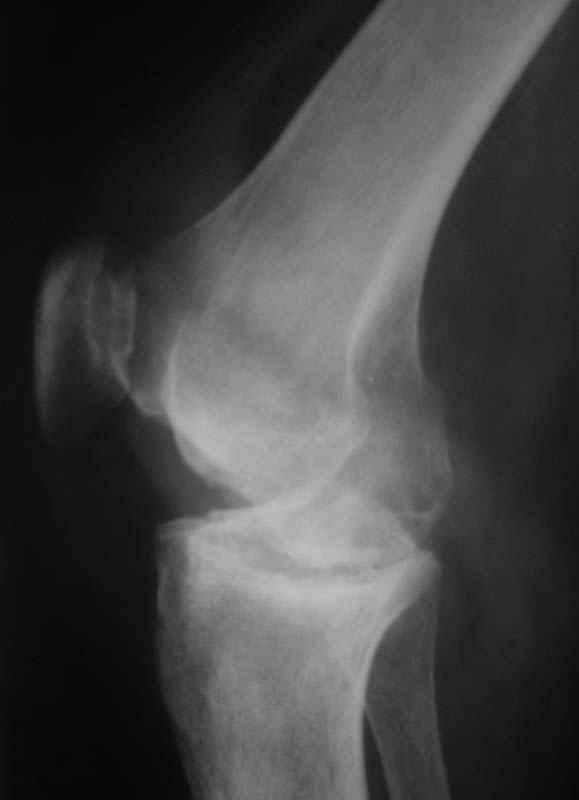

Использована цементная версия с пластикой дна впадины измельченной аутокостью и гранулами гидроксиапатита. Субъективное улучшение после операции. Улучшилось и стабилизировалось общее состояние. В настоящее время затруднено передвижение из-за поражения правого коленного сустава. Болезненный и <болтающийся> сустав. Предполагается замена сустава протезом без сохранения задней крестообразной связки. Возможные варианты? Заранее благодарю! С уважением,А.В.ВладзимирскийДонецкий НИИ травматологии и ортопедииДонецк, Украина

В случаях ревматоидного артрита с деструктивными изменениями сустава мы стараемся применять конструкции типа RT-Solution (Plus) или AGC (Biomet) из-за высокой вероятности нестабильности также и коллатеральных связок. Эти эндопротезы не требуют сохранения связок вообще. Выбор обусловлен также исходной вальгусной (варусной) деформации.